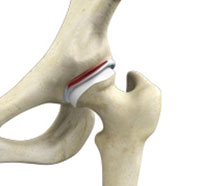

A hip labral tear is an injury to the labrum, the cartilage that surrounds the outside rim of your hip joint socket. The hip joint is a ball and socket joint in which the head of the femur is the ball and the pelvic acetabulum forms the socket.

The hip plays an important role in supporting the upper body weight while standing, walking and running, and hip stability is crucial for these functions. The femur (thigh bone) and acetabulum (hip bone) join to form the hip joint, while the labrum (tissue rim that seals the hip joint) and the ligaments lining the hip capsule maintain the stability of the hip.